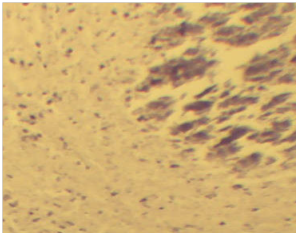

The most characteristic microscopic lesion was tubercle granuloma with central necrosis and calcification. The central area is made of necrotic cellular debris, calcium deposits, and connective tissue capsule walled off the granuloma from the surrounding tissue. The next layers from center to outer were made up of lymphycytes, macrophages, epitheloid macrophages distributed under connective tissue layers (Figure 4A). The frequency of characteristic tubercle granuloma was 4.7% (26/556) (Figure 4B). The presence of concomitant pyogranulomatous and granulomatous lesions in different organs was observed in 7.1% (40/556). Some granulomas were characterized by necrotic foci and intense calcification and fibrosis with absence of epithelioid cells. Multiple small granulomas in the lymph node (Figure 5) with less dense lymphocyte at periphery and epitheloid cells surrounding the deep outer lymphatic layer of the granuloma.

Figure 5 Multiple small granulomas in the lymph node with central necrosis, layer of dense lymphocyte at periphery (double headed black arrows) admixed with epitheloid cells (white arrow). H & E stains.

Multifocal hepatonecrosis with total removal of hepatocytes and infiltration of infilammatory cells (mixed mononuclear and polymorphoneuclear leukocytes) (Figure 6). At the periphery of this central necrosis are huge infiltrations of inflammatory cells (eosinophils, neutrophils and lymphocytes) in the portal triad region. Some foci of hepatic degeneration with swollen hepatocytes.

Figure 6 Multifocal hepatonecrosis with total removal of hepatocytes (black arrows), infiltration of inflammatory cells into portal traiads (double head arrows) and infiltration of inflammatory cells (white arrows). H & E stains.